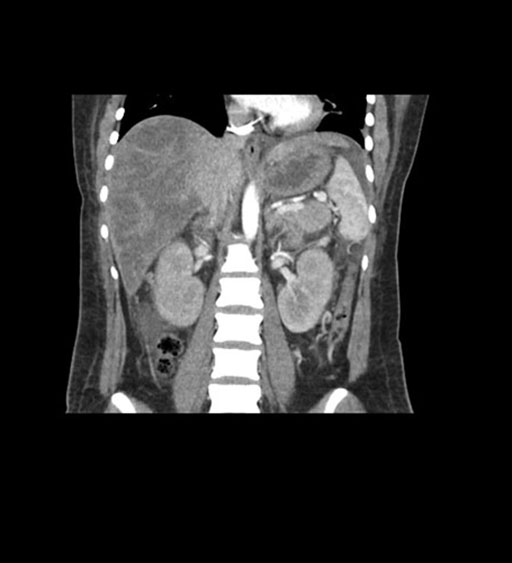

Axial Arterial

Axial Venous

Coronal Arterial

Coronal Venous

Imaging analysis

Based on initial findings, which issue(s) would you be most concerned about?